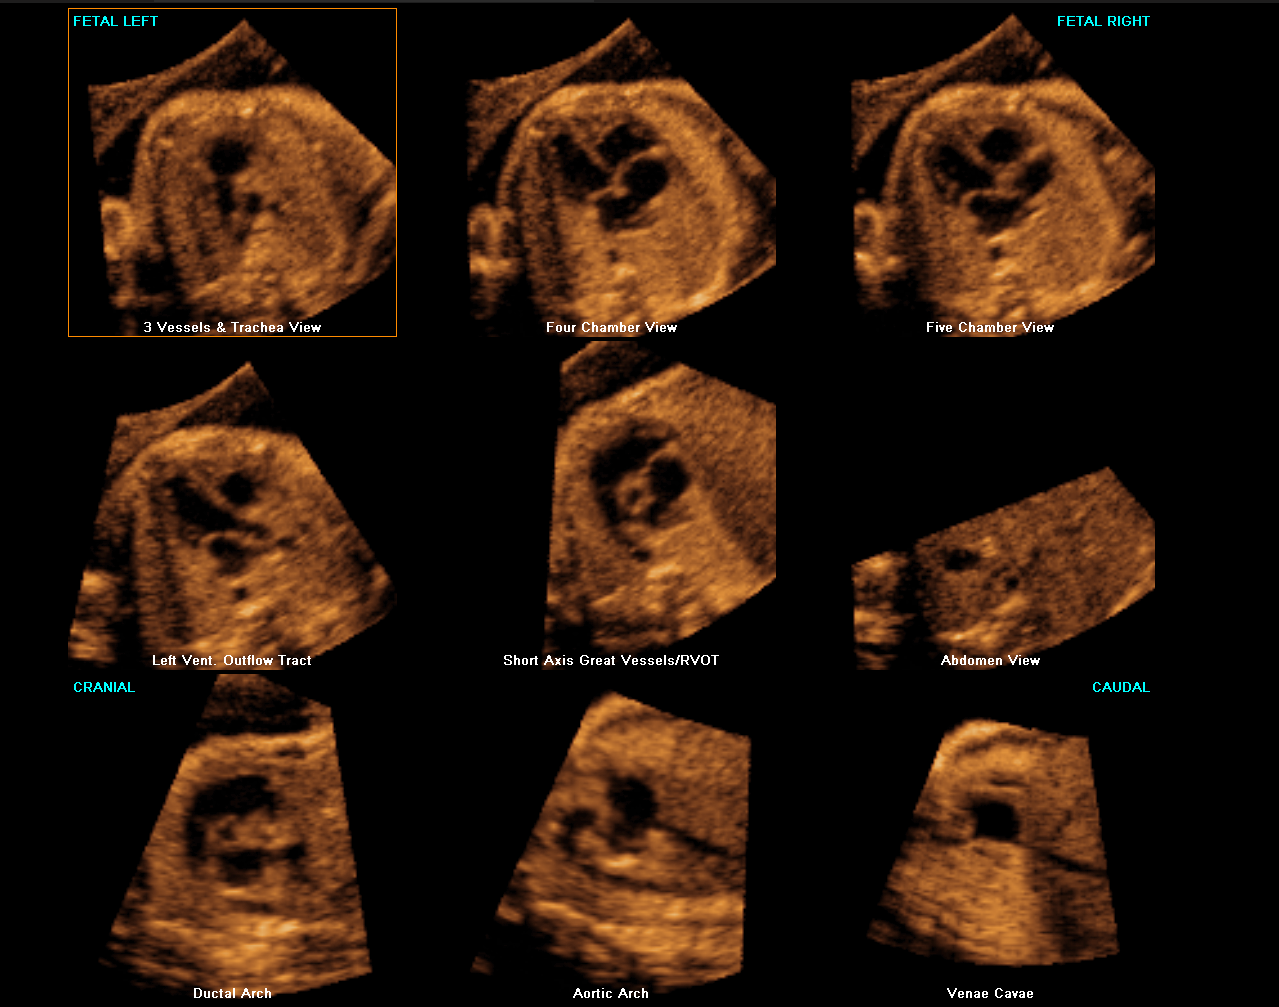

5D Heart™ est un outil intelligent permettant d’établir un diagnostic cardiaque fiable grâce à la visualisation des 9 coupes essentielles, recommandées par les sociétés internationales. Couplé à l’analyse des échanges vasculaires cardiaques, il rend l’examen du cœur plus intuitif indépendamment de la position du fœtus.